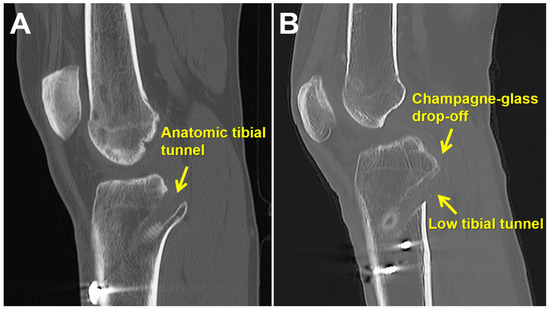

2.2. Surgical Technique

3.2. Tibial Tunnel Position on 3D-CT Scan

4. Discussion